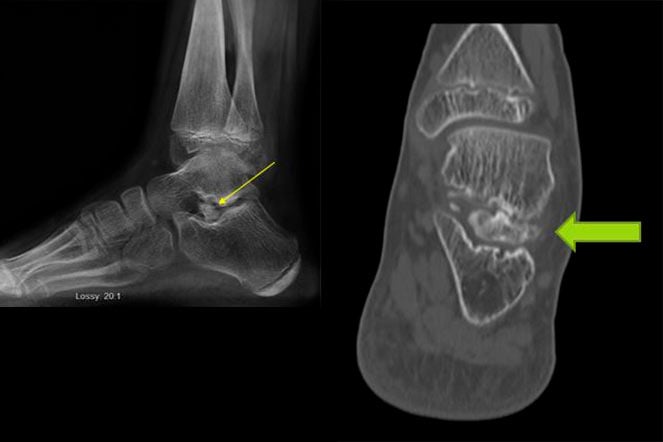

foot X-rays

X-ray imaging of Andrew’s left foot and ankle showed abnormal bone within the joint of the back of the left foot. This was causing a block to the normal motion in this joint.